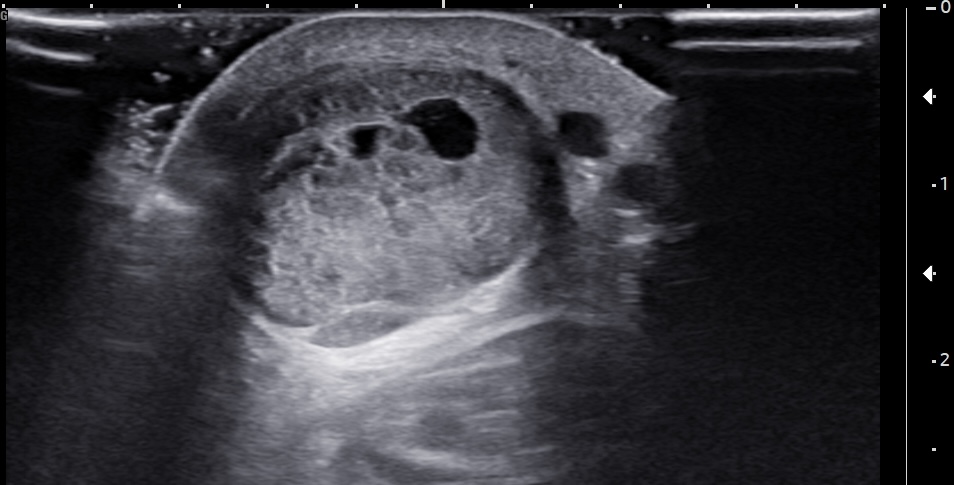

Unlabeled short-axis ultrasound image of the midportion Achilles tendon.